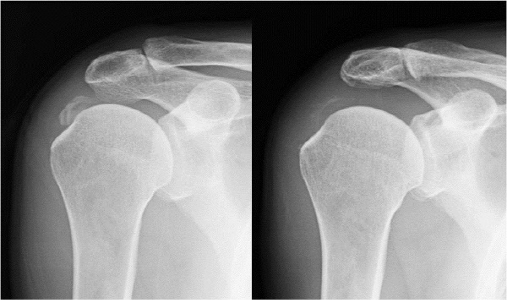

석회화건염은 어깨의 건(힘줄)부분에 석회질이 쌓이는 것이다. 평소에 별 다른 징후가 없다가 갑자기 어깨가 아프다면 석회화건염을 의심해 볼 수 있다.

이 질환의 정확한 발병 원인은 아직까지 정확히 밝혀지지는 않았지만, 노화에 따른 어깨 힘줄의 퇴행 등이 원인으로 알려져 있다. 다른 어깨질환들과는 다르게 처음 석화가 생성되는 시기에는 어깨가 뻐근할 뿐 통증이 거의 나타나지 않는다. 하지만 점차 석회가 커지면서 통증도 심해지고 팔의 움직임이 제한되는 게 특징이다. 이를 방치할 경우 자칫 만성통증이 되어 잘 낫지 않거나 심할 경우 힘줄이 파열될 수 있다.